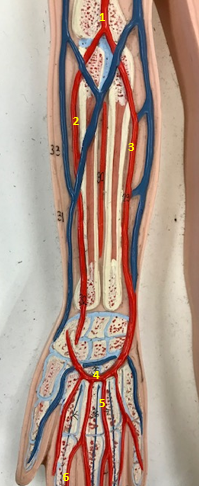

Right radial artery

Name #1

Supplies blood to hand wrist forearm

Function of right radial artery (1)

Right ulnar artery

Name #2

Supplies blood to fingers hand wrist forearm

Function of right ulnar artery (2)

Right brachial artery

Name #3

Supplies blood to arm forearm hand

Function of right brachial artery (3)

Right axillery artery

Name #4

Supplies blood to right armpit and upper limb

Function of right axillery artery (4)

Right brachial artery

Name #1

Right radial artery

Name #2

Right ulnar artery

Name #3